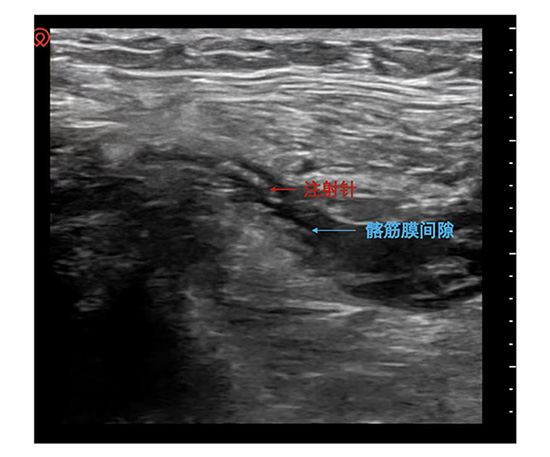

为此,同仁麻醉科将镇痛关口极致前移。一旦骨科医生明确诊断,麻醉医师团队便会迅速响应,携带便携式超声设备前往患者身边。在清晰的超声影像引导下,将局麻药精准注射至支配髋部及大腿前方感觉的髂筋膜间隙内。短短几分钟内,患者原本因任何轻微移动而加重的剧痛得到显著缓解。

一例例救治成功的病例背后,是同仁麻醉科对“可视化麻醉”理念的深入践行与自主技术探索。在髂筋膜阻滞中,便携式高频超声设备成为了麻醉医生的“第三只眼睛”。屏幕上,皮肤、脂肪、肌肉筋膜层、目标神经血管清晰可辨。穿刺针的路径被实时追踪,确保其安全抵达富含神经的筋膜平面,而非血管或实质脏器内。局麻药的扩散过程也一目了然,形成典型的“梭形”液性暗区,标志着阻滞成功。这种可视化技术,将传统的“盲探”操作转变为“直视”下的精准干预,极大提高了成功率,同时将神经损伤、血管刺破和局麻药中毒的风险降至最低。